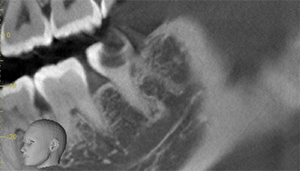

CT

- Before

- After

CTで親知らずと神経(下歯槽管)の位置を確認しました。

親知らずと神経は一定の距離があり、麻痺などのリスクがほとんどないと判断できます。

口腔内

半埋伏の親知らずでした。3糸縫合しました。